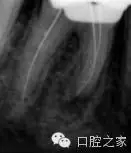

若干雜志均報道了近中牙根內(nèi)第三根管的存在。本篇系統(tǒng)性文獻回顧報道的是2.6%的第三根管發(fā)生率(圖2和3)。為了進一步定位第三根管,需要對開髓洞形進行改良。簡單地講,一旦定位了主根管,并對其進行根管預備后,使用小球鉆或超聲工作尖去除根管口間的牙本質(zhì)橋,為近中根的近中壁與髓腔形成的角提供了直視的視野,將兩個主根管間發(fā)育溝直接暴露出來。然后使用根管口探針探查根管,小號的根管銼順利的通暢根管。除此之外,手術(shù)顯微鏡的運用進一步提高了發(fā)現(xiàn)和治療副根管的可能性。還有一點必須要考慮的是近中根的遠中凹度,為了避免出現(xiàn)帶狀穿孔,第三個近中根管的預備過程要使用小號的根管銼謹慎小心的預備。中間近中根中根管完全獨立的患牙占整個病例中的25%。